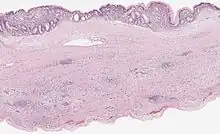

Microscopy

Mucinous cystadenoma of the pancreas